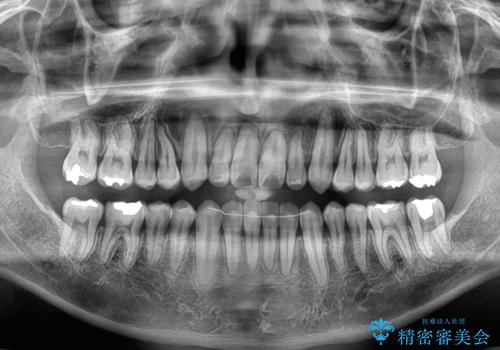

内側に引っ込んだ歯を治したい インビザラインの矯正治療

- 前歯のデコボコとクロスバイトを治したいとのことで来院された患者様です。

上下顎ともに歯列全体の側方拡大とIPR(歯と歯の間を削る)によってデコボコとクロスバイトが解消するように設計し、インビザラインにより治療を行うこととしました。

反対咬合特有の治療途中の前歯の干渉が長く続き、治療中に食事をとりにくく、ご迷惑をおかけしました。

前歯の咬み合わせの調整などを行い、安定した咬み合わせに仕上げることができました。